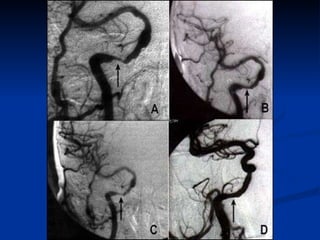

Una  angiografía coronaria , un estudio que se realiza en un laboratorio de cateterización cardíaca. Primero se administra un calmante para relajar al paciente. Luego se inyecta contraste en la corriente sanguínea para producir una radiografía «animada» de la actividad del corazón y el flujo de sangre a través de las válvulas y arterias (lo que se denomina «angiograma»).  El angiograma muestra cuántas obstrucciones hay y cuán graves son. Los médicos a menudo realizan este estudio para determinar cuál sería el tratamiento más eficaz.  ¿Cómo se diagnostica la EAC?

Angiografia Coronaria La angiografía coronaria invasiva sigue siendo fundamental para determinar la factibilidad de la revascularización percutánea y/o quirúrgica.  Está recomendado realizar angiogramas después de la administración intracoronaria de vasodilatadores (nitratos) para atenuarla vasoconstricción y compensar el componente dinámico que frecuentemente hay en los SCA.

Una angiografíacoronaria , un estudio que se realiza en un laboratorio de cateterización cardíaca. Primero se administra un calmante para relajar al paciente. Luego se inyecta contraste en la corriente sanguínea para producir una radiografía «animada» de la actividad del corazón y el flujo de sangre a través de las válvulas y arterias (lo que se denomina «angiograma»). El angiograma muestra cuántas obstrucciones hay y cuán graves son. Los médicos a menudo realizan este estudio para determinar cuál sería el tratamiento más eficaz. ¿Cómo se diagnostica la EAC?

Angiografia Coronaria Laangiografía coronaria invasiva sigue siendo fundamental para determinar la factibilidad de la revascularización percutánea y/o quirúrgica. Está recomendado realizar angiogramas después de la administración intracoronaria de vasodilatadores (nitratos) para atenuarla vasoconstricción y compensar el componente dinámico que frecuentemente hay en los SCA.